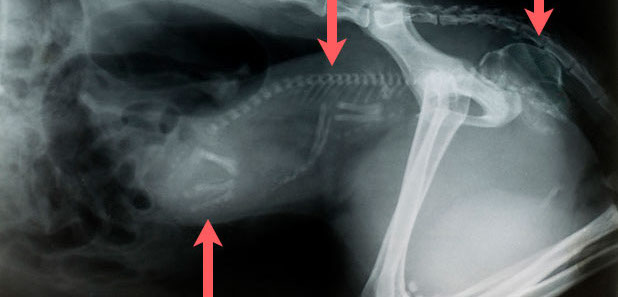

Mehrfachfrakturen nach Autounfall mit Lähmung der Hinterextremitäten, Hund